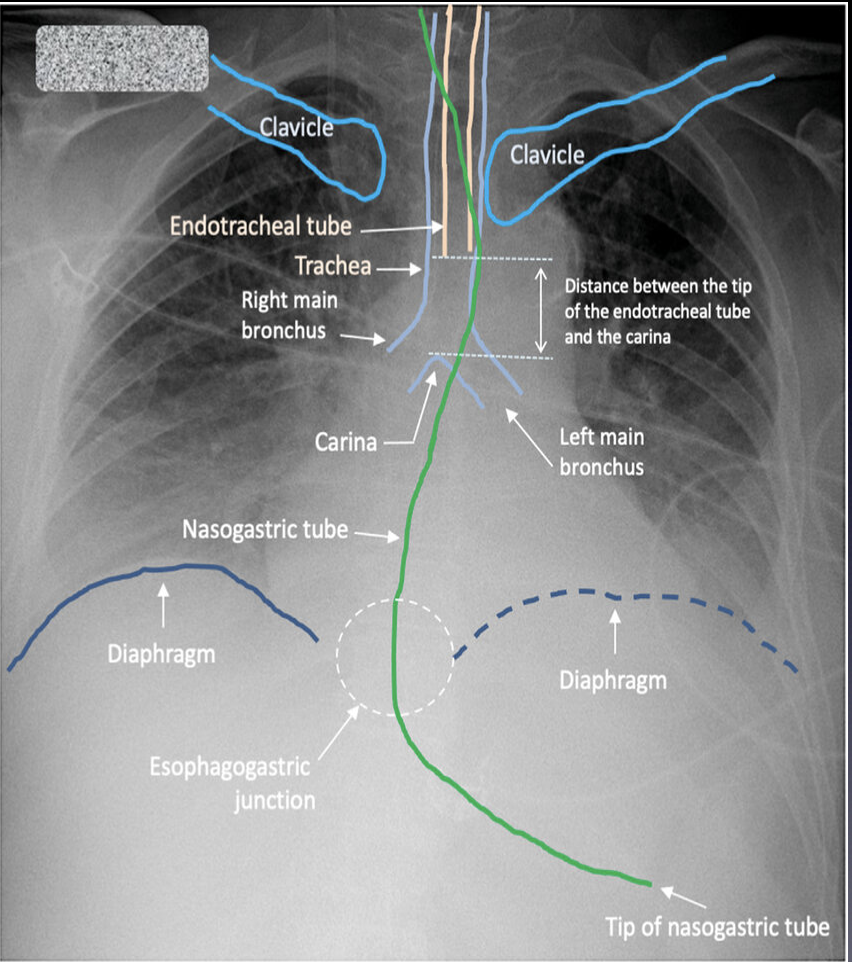

Which CXR landmarks are used when confirming nasogastric tube position ?

1) NGT descends the thorax in the midline.

2) NGT bisects carina.

3) NGT crosses diaphragm in midline.

4) NGT tip sits below the diaphragm

Most tube positions are confirmed by pH of aspirate